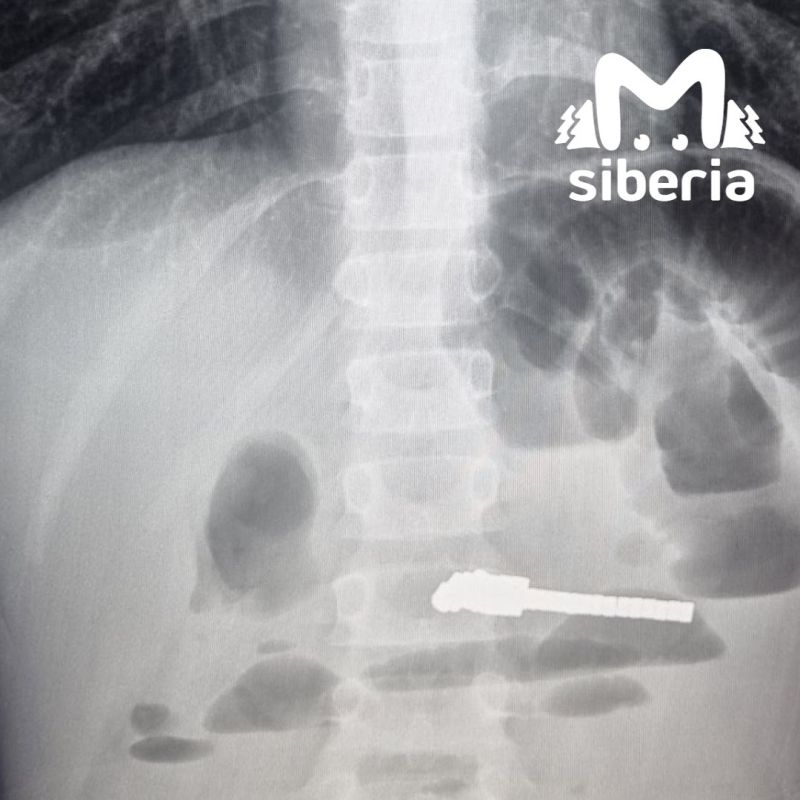

Малыш жаловался на рвоту и сильные боли. Врачи Детской клинической больницы №1 помогли и всё достали. Говорят, что магниты внутри могут притягиваться друг к другу и вызывать серьёзные осложнения. С карапузом, к счастью, всё хорошо.Подписывайся на...

В больницу малыша привезли с жалобами на рвоту и сильные боли в животе. Обследование обнаружило инородные предметы в кишечнике и явные признаки непроходимости. В ходе экстренной операции врачи удалили 25 магнитов.Длительное нахождение этих предметов в...